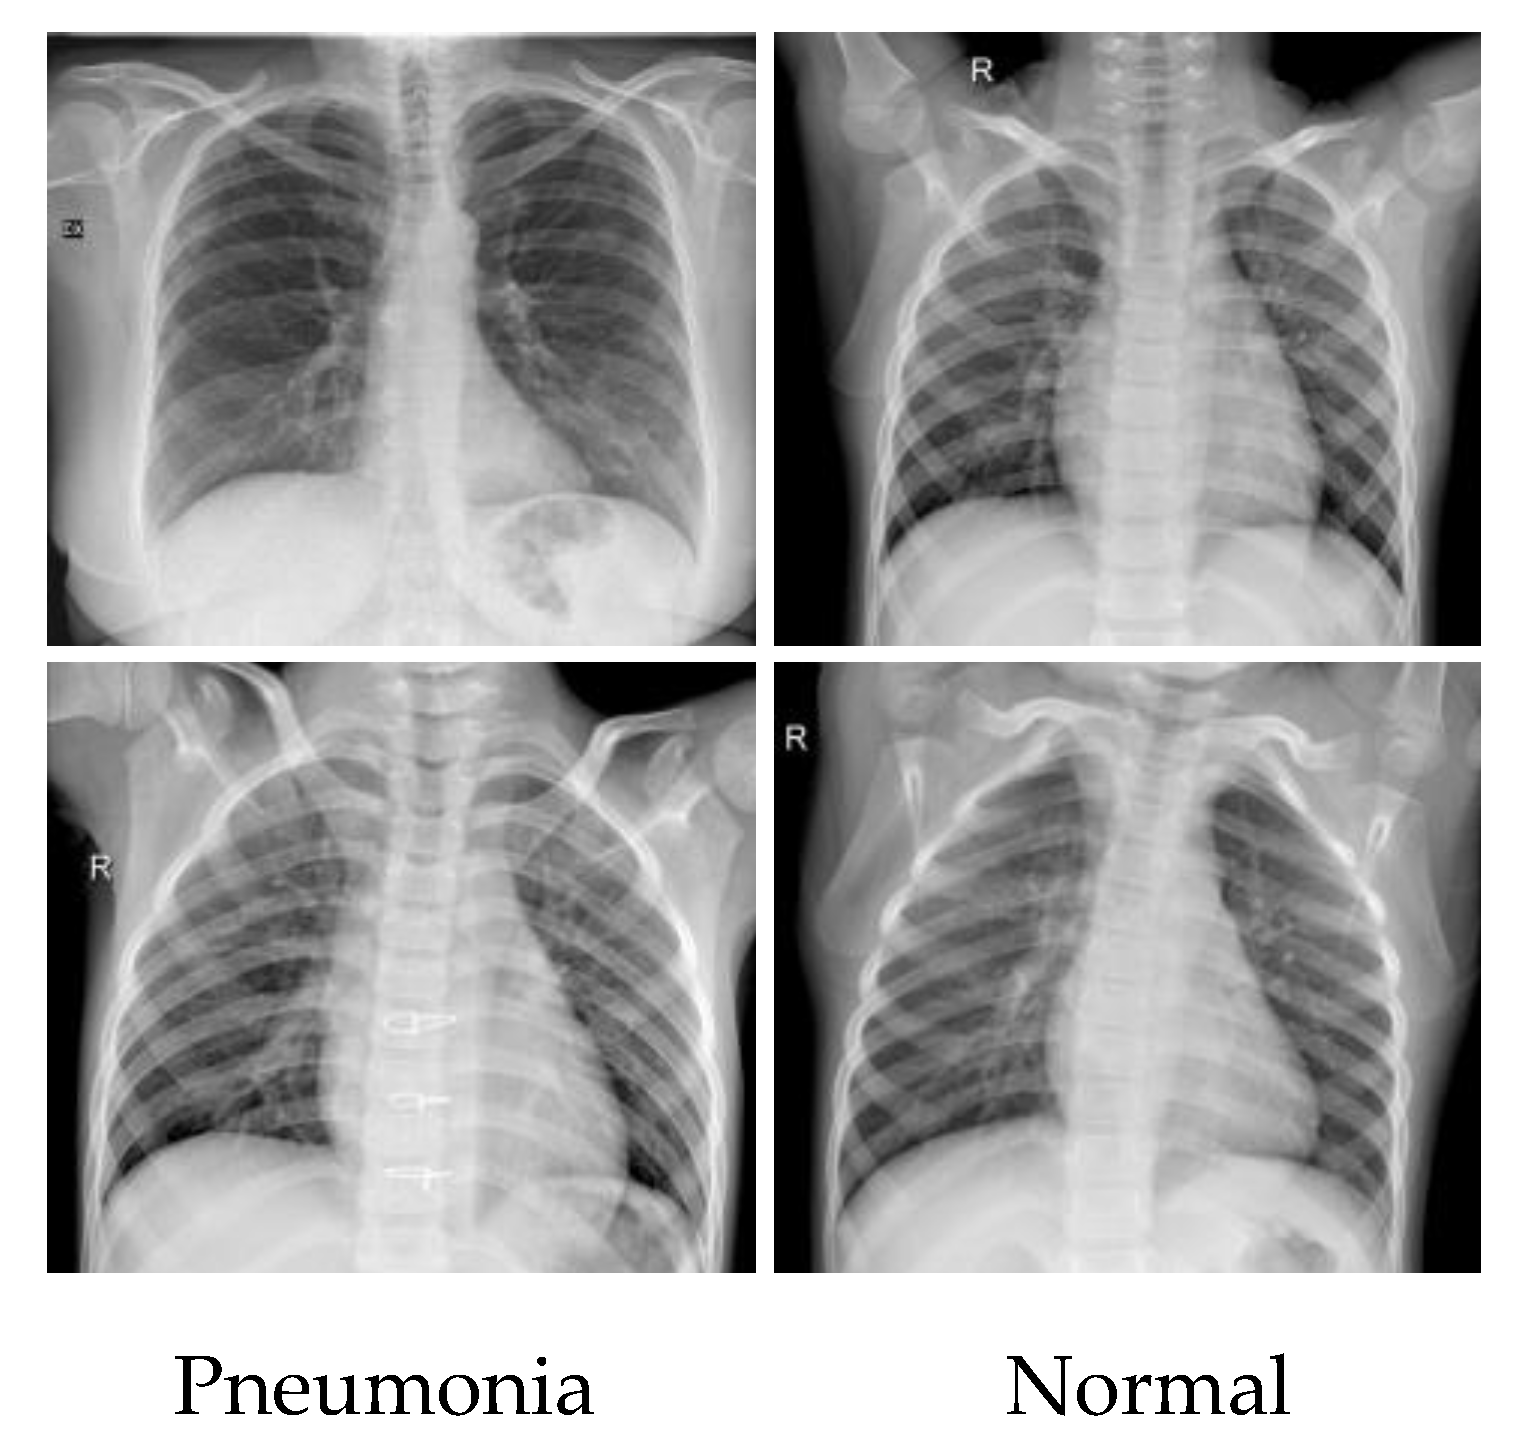

We used the COVID-19 Radiography database [39] as the experimental data, which was obtained by researchers from Qatar University and Dhaka University in collaboration with physicians from Pakistan and Malaysia. The dataset contains 15,169 CXR images from 15,153 patients, including 3616 patients positive with COVID-19 (COVID), 1345 patients with viral pneumonia (Viral), and 10,192 patients with uninfected pneumonia (normal). The partial CXR images of the COVID-19 Radiography database are shown in Figure 2. In the experiments, the dataset is divided into a training set and a testing set in the ratio of 6:4 for training the model with parameters and validating the classification accuracy, respectively. There are 9094 images in the training set and 6059 images in the testing set. The number of images in each category in the dataset is shown in Table 2. To further demonstrate the robustness of our model, another CXR dataset called Coronahack [40] was used. This dataset has 5922 CXR images, includng1576 normal images and 4346 images of pneumonia. The detailed information about the dataset is shown in Table 3. We divided this dataset in the ratio of 8:2 to obtain 4737 images in the training set and 1185 images in the test set, as shown in Figure 3.

Figure 2. The partial CXR images of the COVID-19 Radiography database.